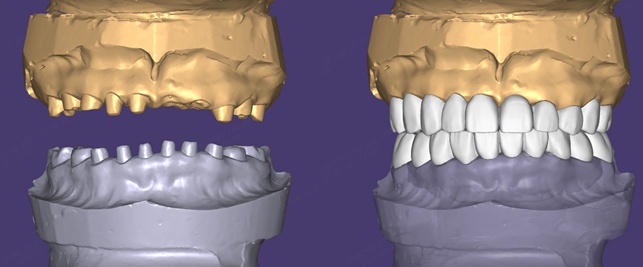

第二步,数字化数据采集。口扫、CBCT、电子面弓三项技术联用,精准复刻口腔三维形态及下颌运动轨迹。这一步的精度直接决定后续修复体的适配度。

第三步,过渡性树脂冠制作。选用树脂材料的逻辑在于:其磨耗特性可随颌骨发育自适应,避免频繁更换。3D打印导板辅助定位,分段粘接微调,确保每颗冠的咬合接触点均匀分布。